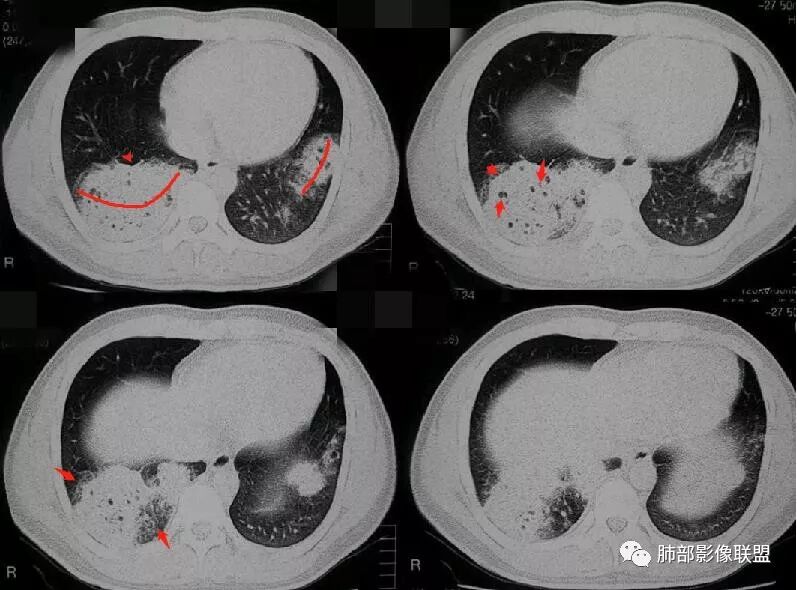

病例二

病灶的形态与分布如何?

右肺中叶及下叶大片实变影及双肺多发腺泡结节,局部成簇的腺泡结节融合成片,以外围及胸膜下分布为主

病灶的走行情况如何?

磨玻璃结节沿支气管飘散并落脚其他肺叶和肺段

病灶边缘情况如何?

以膨隆为主,局部稍平直、收缩

病灶内支气管情况如何?

支气管走形僵直、狭窄、中断,分支减少,呈“枯树枝”改变(图1-4红色短箭头)。可惜没有增强,不能了解病灶强化及血管情况。

病灶内的坏死情况?

有少许小空泡,未见明显液化坏死

周围肺野情况如何?

周围肺野有边界清楚GGO,局部中轴间质明显增厚并呈结节样改变(图1绿色箭头),树芽征不明显

老年男性,有发热、咳嗽、咳少量浓痰,呼吸困难,临床病程不详,但是影像上有实变、簇状分布的腺泡结节及枯树枝征,老年男性,高度怀疑肺炎型肺癌;肺炎型肺癌的病理基础是癌细胞沿肺泡壁、小叶中心、腺泡腔成簇、匍匐性生长,并沿肺泡孔及支气管播散,并且癌细胞分泌粘液引起肺组织实变,液化坏死少见,而干酪性肺结核多有虫噬样空洞及液化坏死区,结核支气管多为壁增厚 、扩张,肺癌的支气管多为狭窄堵塞、粗细不均。

温馨提示:病例2病理结果细支气管肺泡癌此定义取消,现归为腺癌,也是肺炎性肺腺癌的主要类型之一。详细内容请参考肺部影像联盟文章“不同时期腺癌的病理影像诊断”。